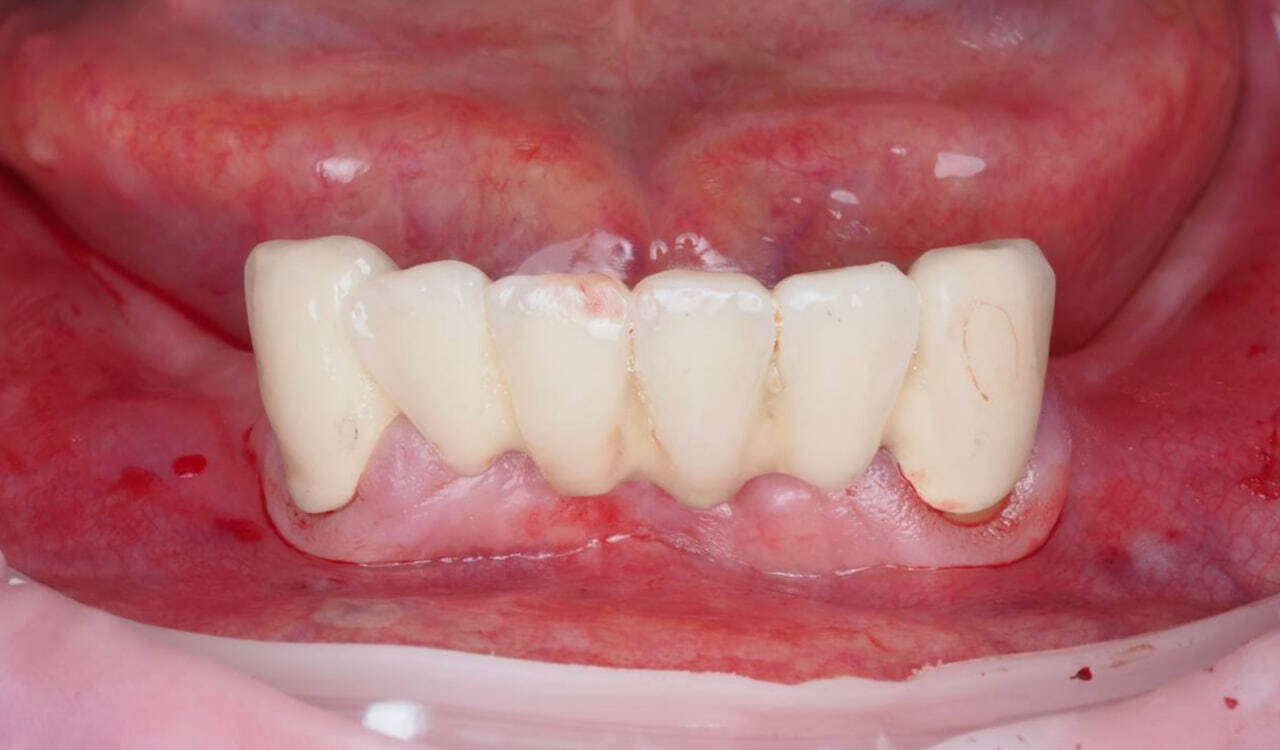

После снятия адаптационного временного протеза прекрасное состояние мягких тканей.